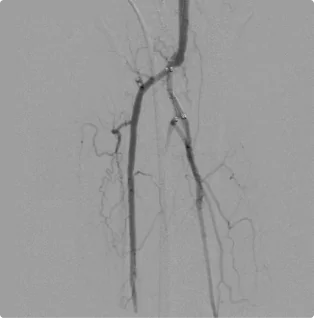

Male – Age 86

Referred by his Podiatrist for his Varicose Veins and Pre-Podiatric Surgical Evaluation

Although this patient was first referred for suspected venous disease, his first ultrasound revealed critical arterial disease in the left calf that placed him at high risk for amputation. The tibial arteries- the branches of arteries that deliver blood to the front and back of the calf- were completely shut off, starving the lower leg of blood and causing severe pain. He was scheduled for intervention the next week. After treating the arteries down the leg and into the foot with atherectomy, angioplasty, and stent placement, Dr. Goldstein restored flow through all three arterial branches and down into the foot. Proper circulation was restored, and the foot was salvaged. Since the first treatment, Dr. Goldstein has closely monitored flow through the arteries to maintain a healthy flow.

Before

Arterial flow through the calf after the intervention. All three arterial branches are present and flowing smoothly, delivering proper flow to the calf and down into the foot to eliminate the need for amputation.

After

Arterial flow through the foot after the intervention. All three arterial branches are present and flowing smoothly, delivering proper flow to the calf and down into the foot to eliminate the need for amputation.